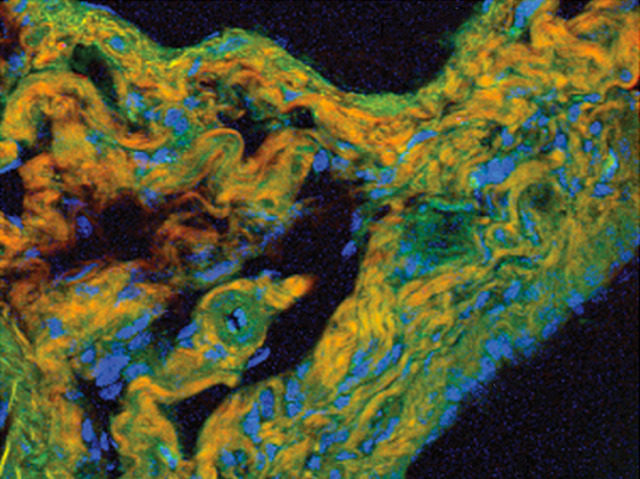

Lasers aren’t just for Bond villains. Intense light beams also have important scientific applications by helping to accurately identify different tissue types. When a laser hits a sample, a tiny fraction of the beam interacts with the organic molecules, whose natural vibrations alter the light's wavelength. As each molecule vibrates at a different rate, the returning light contains a hotchpotch of frequencies that represent a unique fingerprint of the sample's components. This technique can render exquisite detail, like in this mouse liver, where cell nuclei (shown in blue) and different proteins (in orange and green) are all easily distinguished. Until recently though, the necessary trade-offs between speed of scanning and resolution have limited its use in biological and clinical research. But a new technique allows for almost real-time imaging without sacrificing on quality, giving scientists another tool to bring to the fight against the biological bad guys in their secret lairs.